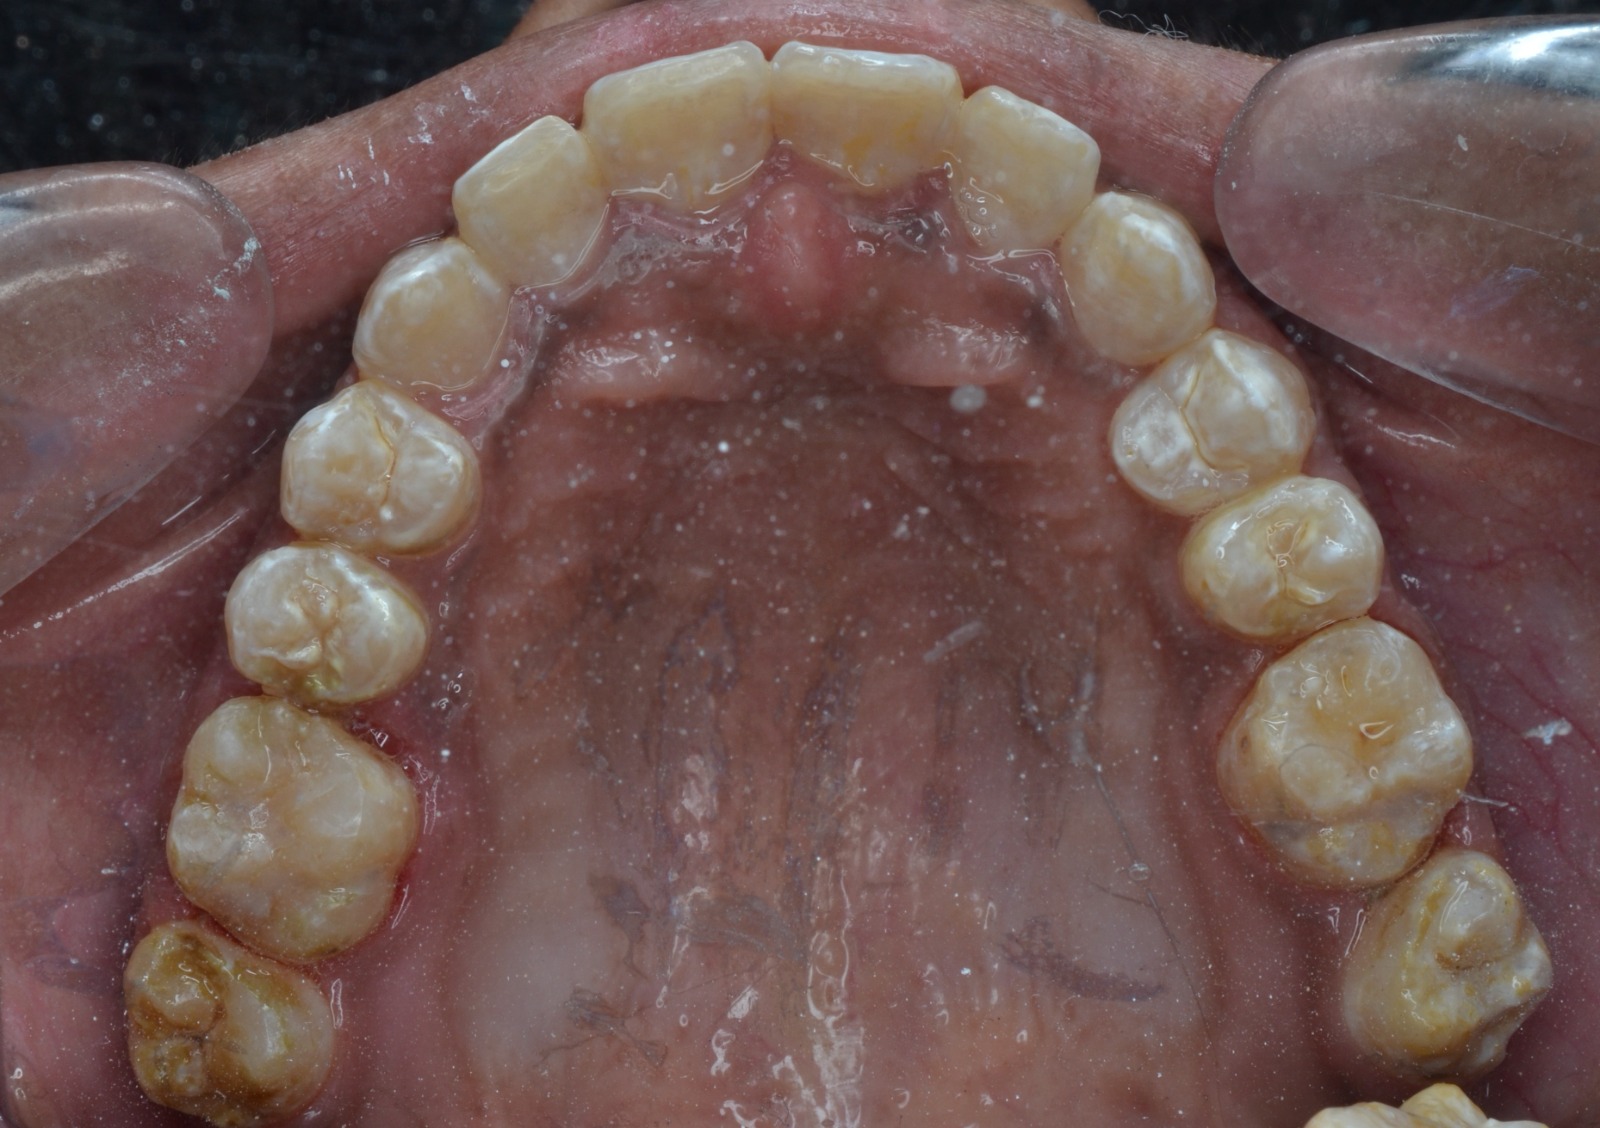

After/Before

See stunning smile transformation before and after

Before After